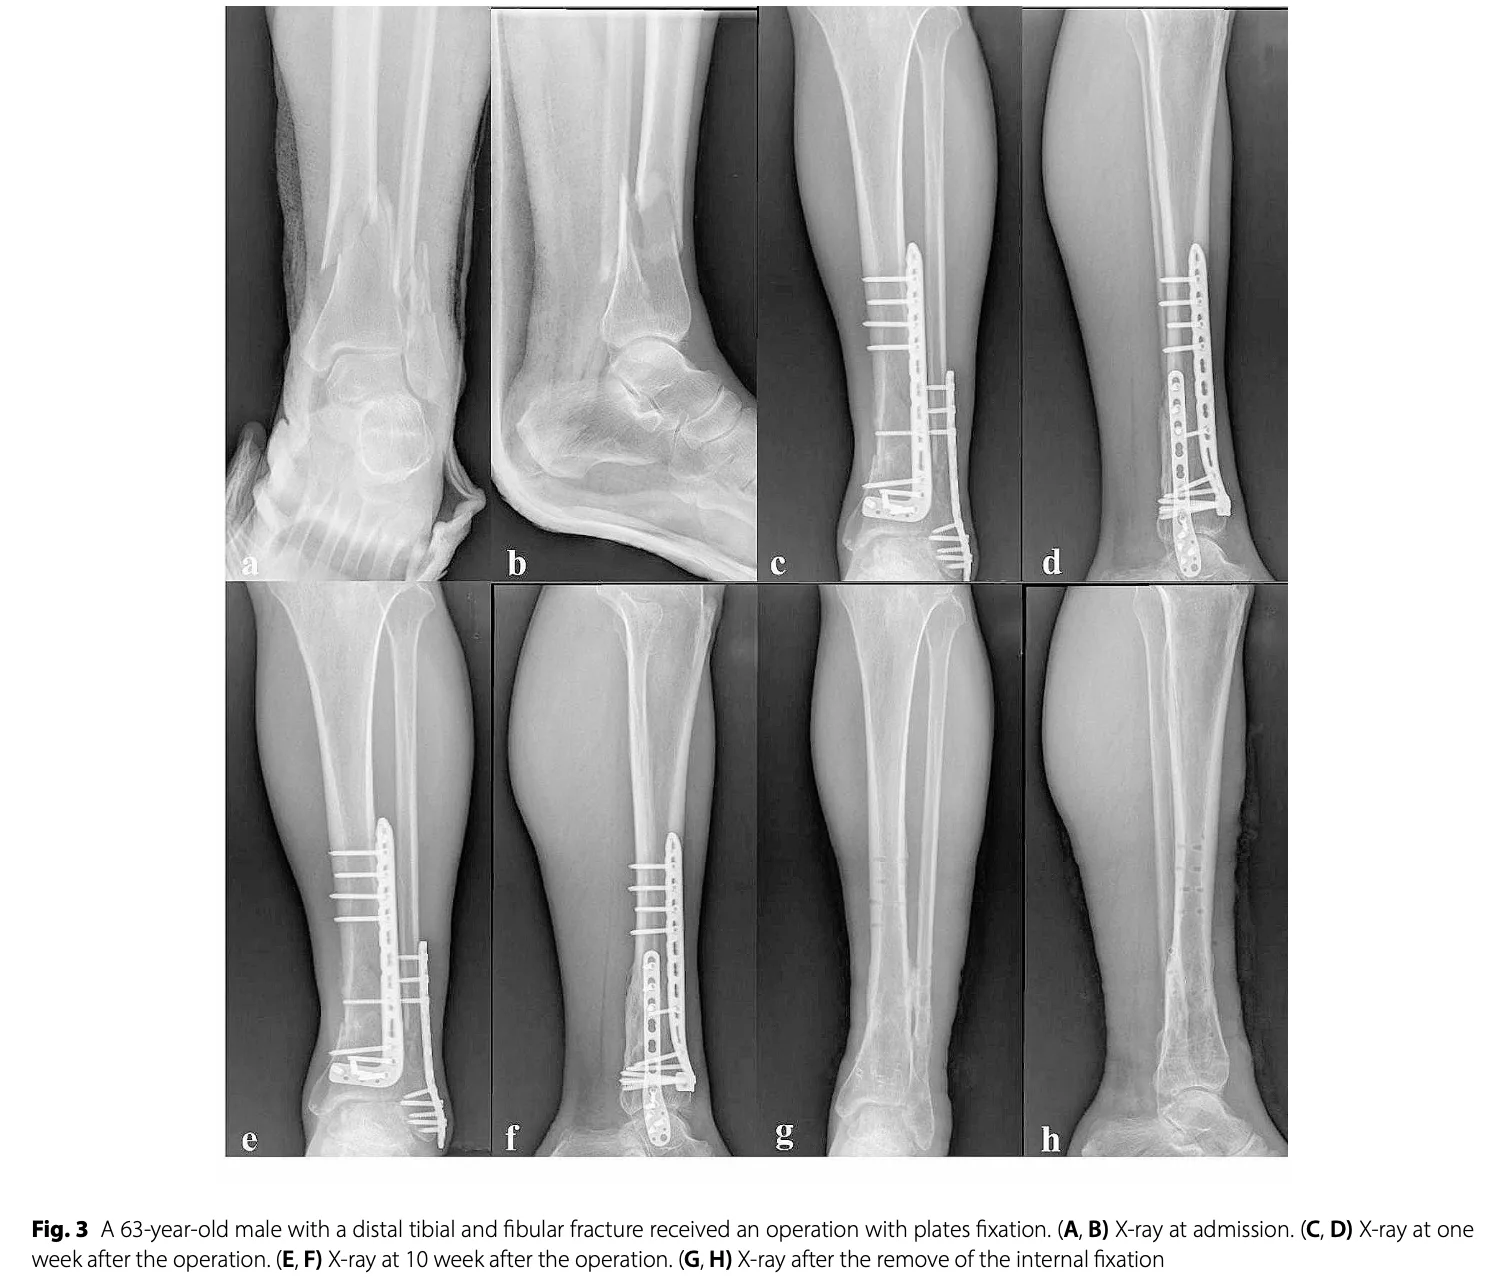

本日は, 脛骨遠位骨幹部骨折・腓骨遠位骨幹部粉砕骨折の中高年患者さんの手術を執刀.

雪道での転倒受傷から2週間あまりが経過し, 腫脹が落ち着いたため, ようやく手術が可能となりました.

プレートを2枚入れる場合, 腫れが引かないと皮膚を縫合することができなくなるため, 腫れが引くまで待機する必要があります.

脛骨・腓骨ともにロッキングプレートというチタン合金製の板とネジで固定.

手術は予定通り, 2時間あまりで終了 しました.